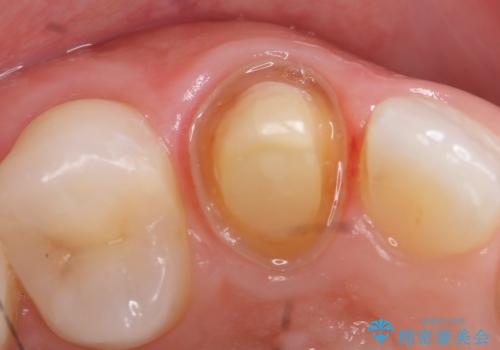

再根管治療終了後、オールセラミッククラウンによる補綴を行いました。

- オールセラミッククラウン(sp)…¥130,000、仮歯…¥10,000、ファイバーコア…¥20,000費用は治療当時の料金となります